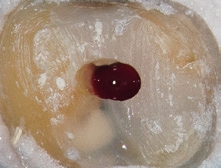

Dr. Brüsehaber: Ich beginne die Trepanation der Pulpakammer sehr gern mit einer Diamantkugel (z. B. 6801L, Komet) (Abb.1). Wenn ich damit das Pulpencavum direkt eröffnen kann, gilt es, im nächsten Behandlungsschritt die Hartsubstanzüberhänge abzutragen, um einen „straight line access“ zu den Wurzelkanälen zu schaffen (Abb. 2 und 3). Ein geradliniger Zugang ist essentiell für alle weiteren Behandlungsschritte. Mit ausreichender Erfahrung und unter Verwendung eines Operationsmikroskops ist es möglich, das Wurzelkanalsystem auch über eine sehr kleine Zugangsöffnung zu behandeln.